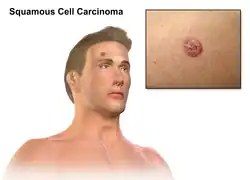

Carcinoma de células escamosas da pele

| O carcinoma espinocelular da pele tende a surgir a partir de lesões pré-malignas. A superfície é geralmente escamosa e muitas vezes forma úlceras (imagem). | |

Carcinoma espinocelular ou carcinoma de células escamosas é um dos principais tipos de cancro da pele, a par do carcinoma basocelular e do melanoma.[10] Geralmente apresenta-se na forma de um nódulo duro na pele com superfície escamosa, embora possa também formar uma úlcera.[1] A doença desenvolve-se ao longo de meses.[4] O carcinoma espinocelular tem maior probabilidade de se espalhar para outras partes do corpo do que o carcinoma basocelular.[11]

O CCE geralmente começa como uma crosta vermelha e escamosa ou como um nódulo firme vermelho ou como uma úlcera elevada. Geralmente é áspero e forma uma crosta que pode coçar e sangrar quando raspado. Cresce lentamente e pode se tornar doloroso.[16]